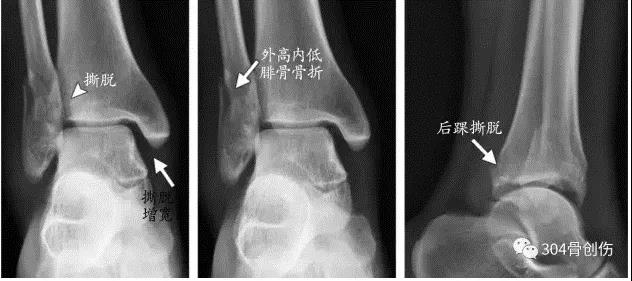

下胫腓损伤与骨折及类型 Lange-Hansen分类

- 1.旋前外旋:最常见

- 2.旋前外展:可发生

- 3.旋后外旋:较常见

- 4.旋后内收:不发生

下胫腓联合损伤诊断

术中判断外旋应力试验::内侧间隙增大超过2毫米提示损伤Hook test:在内外踝骨折固定后,用尖钩向外拉腓骨,如腓骨向外移动大于4mm,则表明下胫腓联合韧带完全撕裂